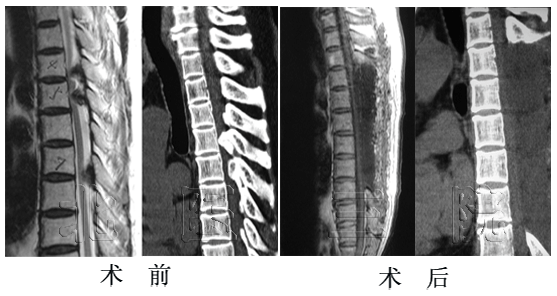

男性,53岁,胸椎管狭窄症(T12-L2椎间盘突出伴骨化),行后路T12-L2经关节突椎间隙外侧缘入路脊髓腹侧减压、固定、融合术。